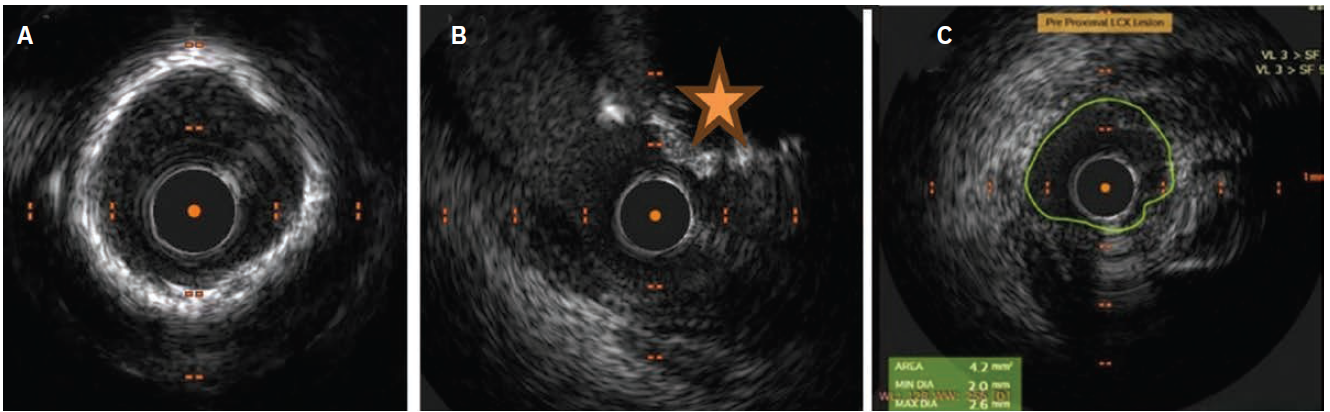

The LCx was crossed with a Fielder FC guide wire and IVUS showed heavy calcification with calcific nodules. IVUS Calcium Score: 3; (Calcium ≥270 with ≥5 mm:1, 360-degree Calcium:1, Calcium Nodule:1, vessel diameter ≤3.5 mm:0) (Figure 2A-2C). Orbital atherectomy was done with a 1.25 mm burr at 120,000 rpm in the LCx (Video 2) followed by dilatation with a 3.5 mm x 10 mm cutting balloon. LMCA to LCx crossover stenting was done with a 3.5 mm x 28 mm drug-eluting stent, ensuring overlap with the in situ LCx stent, and proximal optimization technique (POT) of the LMCA was done with a 5 mm x 8 mm balloon. A a 4 mm x 10 mm NC balloon was used for post dilatation of the LCx, followed by kissing balloon inflation of the LAD/LCx (Figure 3A-3E).